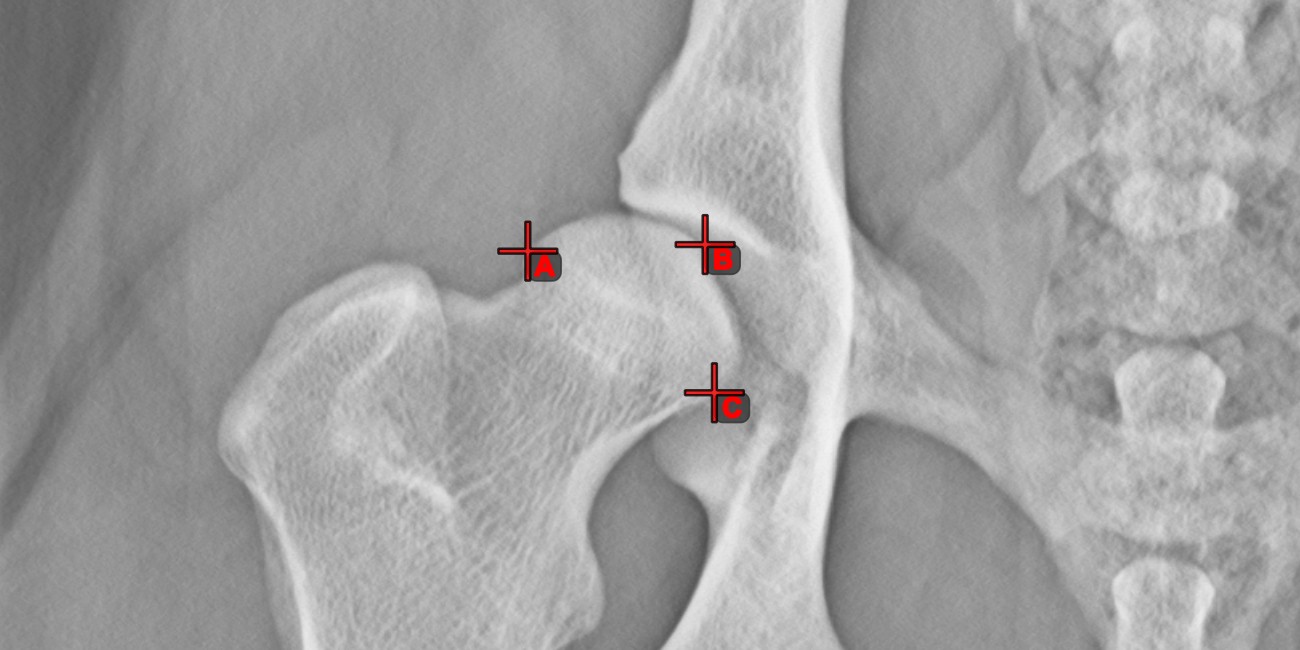

Measurement Point¶

Measurement Point tool. Each point is assigned with a letter for better identification.Select/Move Item tool. Select the point by using the assigned mouse button of the tool, and then move it freely anywhere on the image.